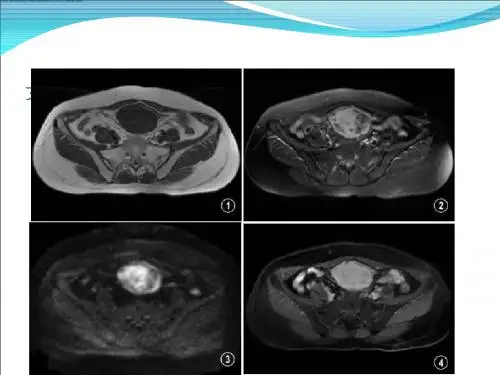

156腹内型侵袭性纤维瘤病与间质瘤CT鉴别诊断的应用价值罗崇军腹内型侵袭性纤维瘤病(intra-abdominal aggressive fibromatosis,IAF)是临床之中较为少见的严重病症。

由于疾病的特殊性和少见性,较为容易同间质瘤(gastrointestinal stromal tumors,GIST)相混淆,一旦误诊对于患者影响很大。

两种疾病的临床表现较为相似,甚至很多影像学检查也不容易区分,这就增加了诊断之中的难度。

CT影像检查技术作为目前较为有效的诊断方式,应当深入进行两种疾病的影像学区分,以此保障患者的准确治疗。